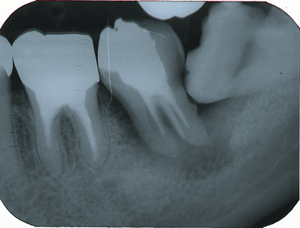

40歳女性 左下8を左下7へ自家移植

左下7は根尖にいたるまで感染が進み、抜歯しなければなりません。

すぐ後ろにある智歯を移植することにしました。

抜歯した左下7です。

2004.4.22移植した親知らずです。

移植に用いた左下智歯です。

移植当日です。